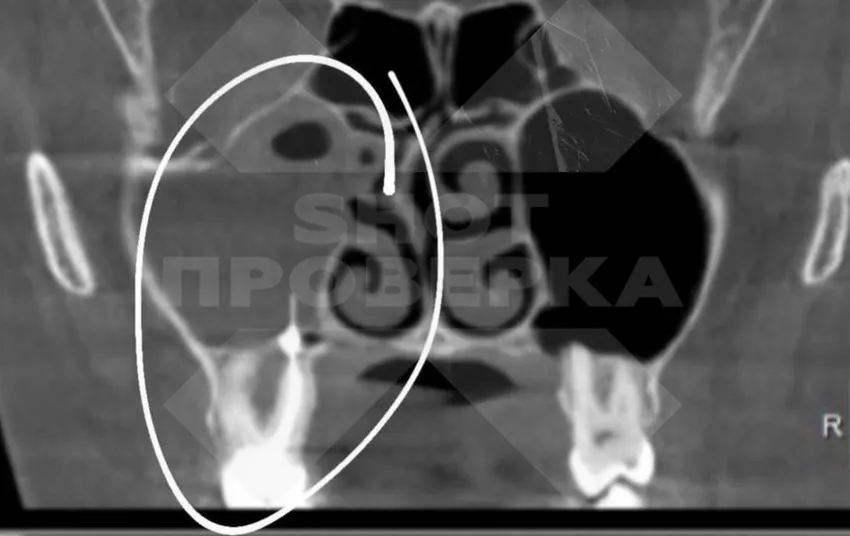

О проблеме Татьяна узнала благодаря врачу-ортодонту, у которого хотела установить себе брекеты. Сделав снимок, мужчина заметил в носовой пазухе пациентки некие посторонние предметы. Оказалось, что три пломбы и кусок инструмента попали в нос девушки в тот момент, когда в далеком 2009 году ей лечили пульпит и прочищали каналы зуба.

Тогда Татьяну направили на экстренную операцию. Оказалось, что из-за забытых врачом вещей в носовой пазухе девушки выросла мицетома, грибок. Он полностью заполнил собой одну из пазух. Если бы ситуация ухудшилась, россиянка могла начать страдать от гайморита, менингита, энцефалита и остеомиелита челюсти.